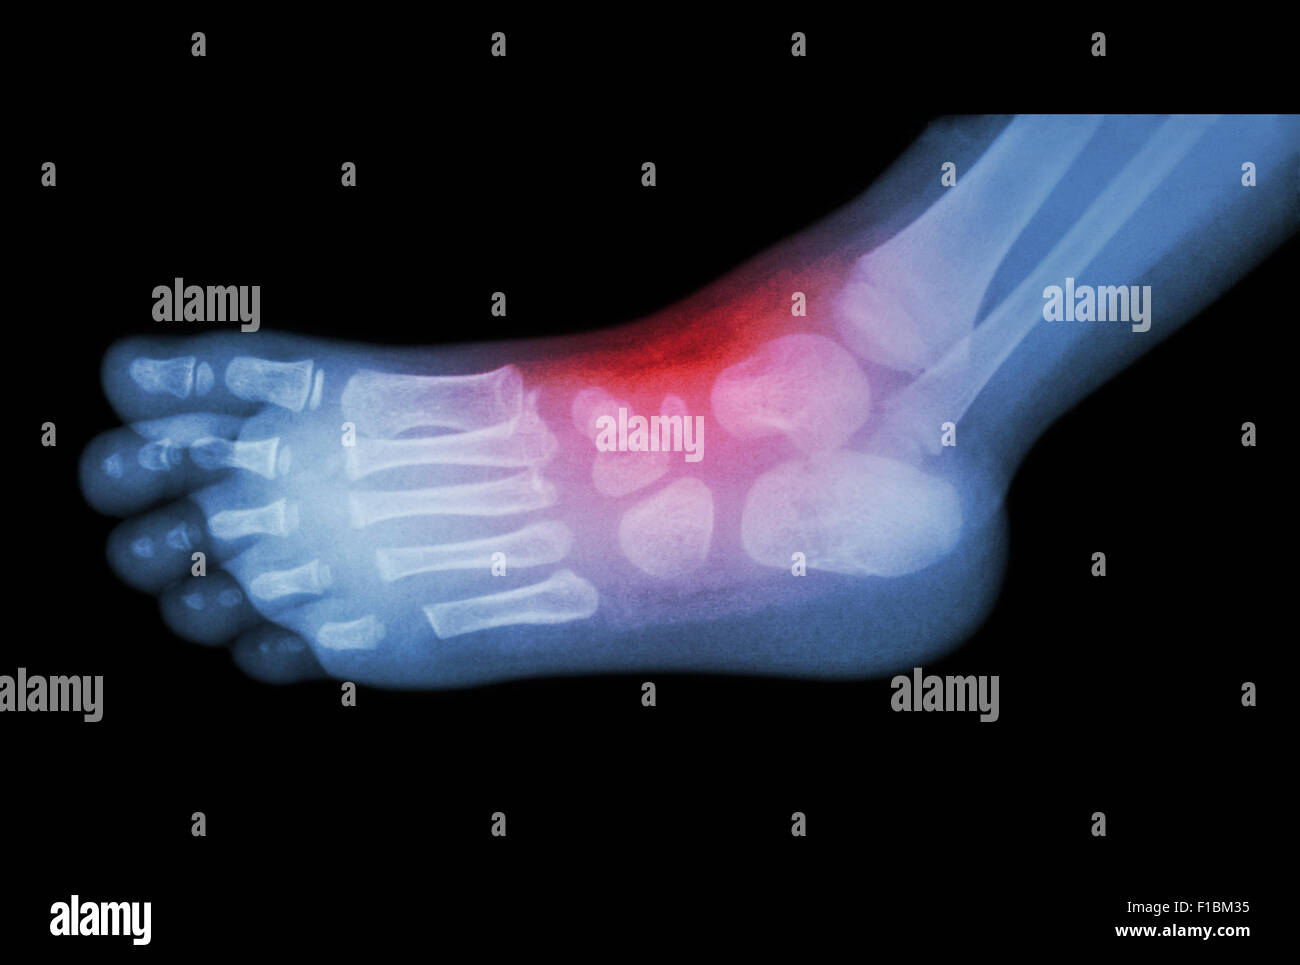

From www.alamy.com

Arthritis and injury at ankle film xray of child 's foot ( side view Arthritis After Ankle Dislocation Traumatic injuries of the ankle. management of ankle arthritis after severe ankle trauma could pose different and difficult challenges in treatment compared. posttraumatic osteoarthritis of the ankle is the primary cause of ankle arthritis. osteoarthritis of the ankle is common but it's not the only kind of arthritis that can affect the bones of the feet and. Arthritis After Ankle Dislocation.